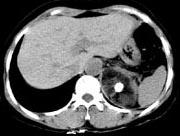

问题 男性,28岁,左腰背酸胀5个月,CT检查如图所示,应诊断为 ( )

选项 A、左肾上腺腺瘤 B、左肾上腺转移瘤 C、左肾上腺错构瘤 D、左肾上腺嗜铬细胞瘤 E、左肾上腺髓样脂肪瘤

答案 C